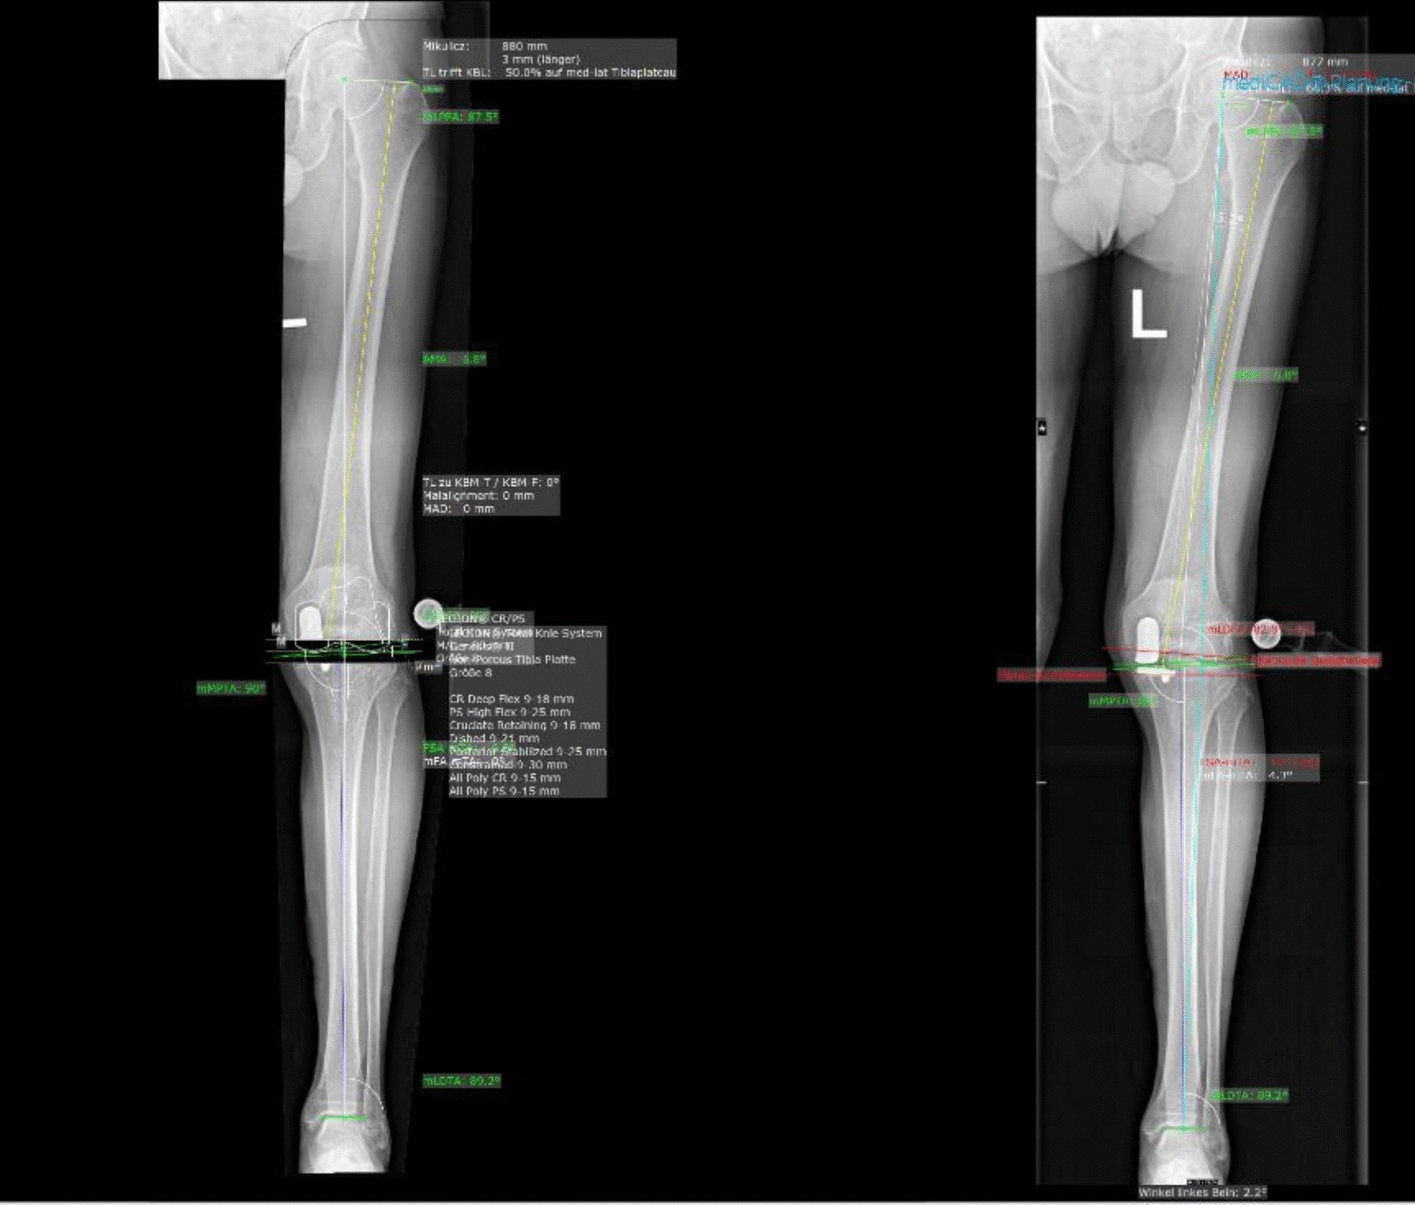

Methods: Imaging of patients who underwent revision surgery of a medial UKA to TKA for aseptic loosening of the tibial or femoral component was retrieved. Lower limb axes were evaluated using anteroposterior plain radiographs of the leg using the software MediCAD Knie 2D (mediCAD Hectec GmbH, Altdorf, Germany). The radiographic axes of revised patients were compared with established reference values, as defined by the MediCAD Knie 2D software and published literature, to identify common alignment patterns potentially associated with aseptic loosening.

Results: Data from 62 patients were analysed. Before the revision surgery, the joint line convergence angle (JLCA, P = 0.002) and the anatomical-mechanical angle (AMA, P < 0.0001) were statistically significantly greater than the corresponding reference values. In contrast, the mechanical lateral distal femoral angle (mLDFA, P < 0.0001), the mechanical and anatomical medial proximal tibial angle (mMPTA and aMPTA, P < 0.0001), and the mechanical and anatomical lateral distal tibial angle (mLDTA and aLDTA, P < 0.0001) were significantly lower than reference. No statistically significant difference was found in the mechanical lateral proximal femoral angle (mLPFA, P = 0.9) or in the mechanical axis deviation (MAD, P = 0.5) when compared to normative data.

Conclusion: Our cohort of patients revised from medial UKA to TKA for aseptic loosening frequently exhibited consistent deviations in lower limb alignment, particularly increased AMA and JLCA, and reduced mLDFA, mMPTA, and mLDTA. These subtle but recurrent patterns may alter load distribution across the medial compartment, contributing to implant micromotion and loosening. A detailed preoperative axis assessment may help identify patients at a higher biomechanical risk.